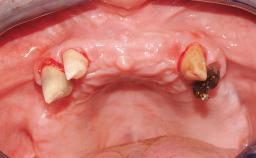

In this video Dr. Nikos Mattheos demonstrates the full diagnostic, planning and treatment sequence of an immediate implant with an immediate prefabricated provisional restoration in the esthetic zone. A 28 years old female patient presents with discoloration and increasing mobility of tooth 11. Advanced stage of external resorption is diagnosed. Patient's high esthetic demands combined with intact gingival architecture and periodontal health makes her a good candidate for immediate placement and restoration to preserve the gingival contour. Surgical and restorative treatment is planned with digital workflow based on data from CBCT and intraoral scan. An immediate temporary crown is manufactured for placement at the day of the surgery. Flapless extraction is performed, and the implant placed with guided surgery. Consequently, the buccal gap of the socket is augmented with Xenograft, while the soft tissue space maintained with a collagen plug. Finally, a provisional crown is immediately placed on the implant with a titanium temporary abutment and an emax prefabricated crown.

Timing of placement Immediate Placement (extraction sockets) (Type I)

Radicular morphology Uniradicular

Available apical bone to achieve primary stability Sufficient height ( ≥ 4 mm) and width (> 2 mm around apex of planned implant)

Socket walls Intact

Thickness of buccal wall less than 2 mm

Anticipated residual defect after implant placement 2 mm or less